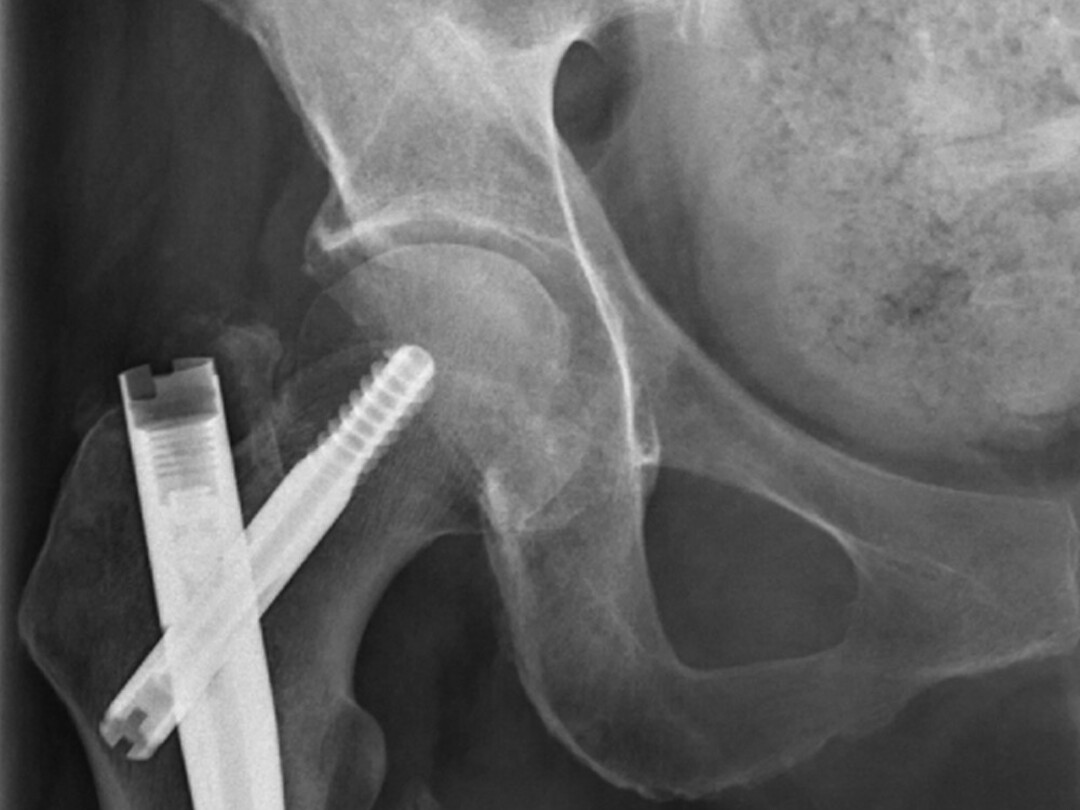

Bilaterale femurfractuur bij bisfosfonaatgebruik

Röntgenbeeld

In dit artikel beschrijven we een patiënte met beiderzijds een atypische femurfractuur. Zulke fracturen ontstaan spontaan of na minimaal trauma bij patiënten die langdurig een bisfosfonaat gebruiken. Denk bij deze patiënten aan alternatieve medicamenteuze fractuurpreventie.

Langdurig gebruik van bisfosfonaten kan leiden tot een spontane femurfractuur. De incidentie van deze fracturen is 1,74 per 10.000 persoonsjaren en neemt toe met de behandelduur van bisfosfonaten. Bij zo’n spontane fractuur is chirurgische fixatie de voorkeursbehandeling. In een eerder stadium kunnen patiënten ook hulp zoeken vanwege onbegrepen bovenbeenspijn. Dit kan bij de huisarts zijn of de voorschrijvend specialist, zoals de internist of reumatoloog.

Alle betrokken hulpverleners dienen bedacht te zijn op de klachten die passen bij een dreigende pathologische fractuur door bisfosfonaatgebruik. Wanneer er bij aanvullend radiologisch onderzoek aanwijzingen zijn voor een dreigende atypische femurfractuur, moet er worden overwogen…